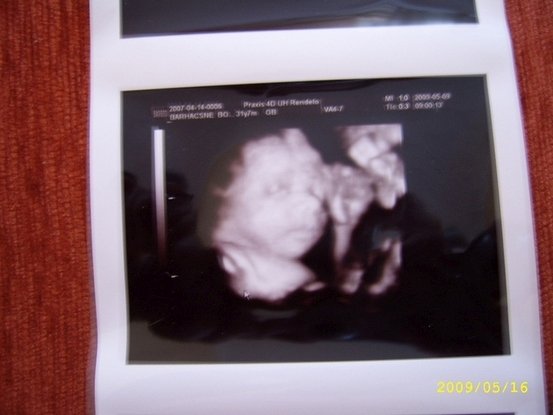

Brigi, de jó az UH kép. Praxis rendelő?? én is ott csináltattam Kolos 4D-jét. :lol:

Renáta: Igen, van rajta egy 2007-es dátum, mert Petyával is itt voltunk, így az adatokat nem rögzítették újra. Viszont Orsinak igaza van és jobb felül van a 2009-es dátum amikor ksézült. Egyébként így uh kép alapján tiszta Petya :-))

Orsi: Igen praxis! Náluk voltunk Petyával is és most is oda mentük. Szerintem jók az áraik is és nekem nagyon szimpik voltak! Petya igen az édeset szereti, de az nagyon!!

Lilluska: Köszönöm szépen!!! Nem dícsekvésképp, de a szonográfus a praxisban is azt mondta, hogy milyen szép baba :oops: